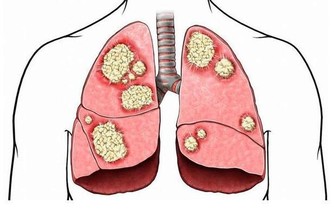

西醫的檢查是病變的結果檢查,只有到了身體通過量變的積累達到了質變時候才能檢查出來。這是為什麼有的人心悶、頭痛全身不舒服,到醫院卻什麼也檢查不出來的道理。這就是為什麼癌症只有到了晚期才能檢查出來的原因,因為早期不叫癌症,早期就叫高血壓、糖尿病、腎炎、乙肝、風濕、哮喘、附件炎等等。"